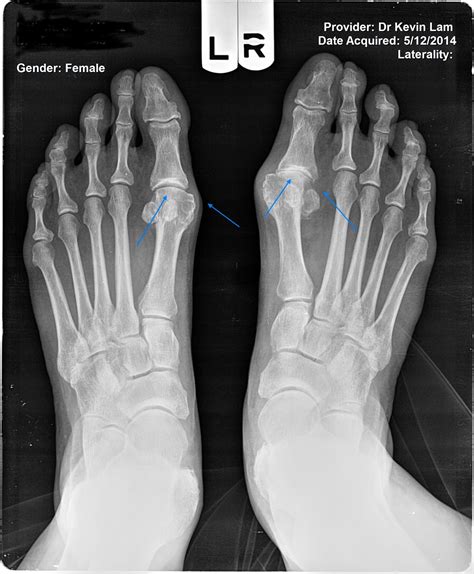

• Measuring the Angle: Doctors measure the Hallux Valgus Angle (HVA) and the Intermetatarsal Angle (IMA) to quantify the severity of the bunion.

• Joint Health: Identifying cartilage loss or the presence of bone spurs within the joint space.

• Identifying Associated Deformities: Often, bunions coexist with hammertoes or flat feet, which can be identified on the same film.

Once the images are captured, a radiologist or your podiatrist will analyze the films. They look specifically at how the first metatarsal bone has deviated away from the second metatarsal. The following table illustrates how medical professionals generally categorize the severity based on the angles derived from the X-ray: